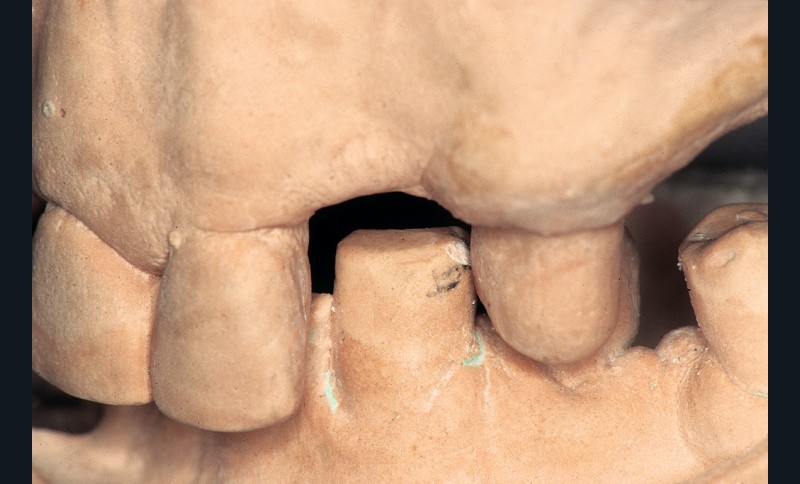

Sens vertical : la hauteur prothétique utilisable (HPU) correspond à la distance séparant le sommet de la crête des dents antagonistes ou du plan occlusal. Dans l’idéal, au niveau antérieur, cette hauteur est d’environ 4 mm et au niveau postérieur d’environ 7 mm (fig. 1).

Sa réduction se révèle être, souvent, un obstacle majeur à la réalisation d’une reconstitution prothétique satisfaisant…